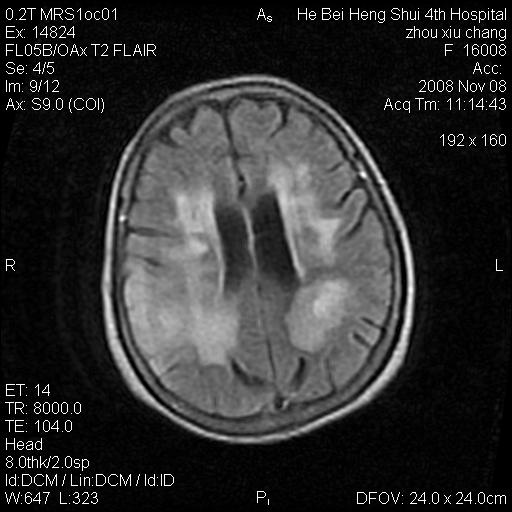

两种可能:1,转移瘤,2,脑炎,建议增强扫描

多发硬化(年龄不太支持)待排转移瘤

转移瘤?淋巴瘤?

形态及整体病灶看起来首先考虑转移瘤或淋巴瘤,但奇怪的是多个病灶周围均未见显著的水肿区,这不符合这两个肿瘤的特点,结合ct表现及患者病史有个人考虑是否有皮层下动脉硬化性脑病伴多发胶质增生可能.

考虑  皮层下动脉硬化性脑病伴脑炎或

不像占位性病变,考虑脱髓鞘改变

1皮层下动脉硬化性脑病,2胶质增生。

皮层下动脉硬化性脑病伴脱髓鞘改变!

脑白质病

不除外转移瘤,建议增强

支持:皮层下动脉硬化性脑病伴脱髓鞘改变。